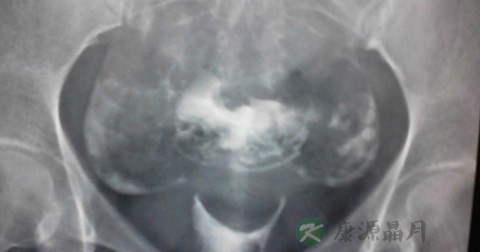

1、输卵管通而不畅:推注造影剂有阻力,造影剂进入盆腔缓慢,在停注造影剂十数分钟后,可见造影剂在盆腔内弥散,但弥散欠佳。

2、输卵管积水:造影剂积聚在输卵管内,输卵管异常扩张呈囊状或腊肠状,以远端明显,多伴有输卵管伞端阻塞。盆腔内一般无造影剂影弥散。

3、输卵管通畅:子宫充盈呈倒三角形,两侧输卵管像细虫样弯曲在子宫两侧,造影剂先充盈输卵管近端的狭部,然后迅速向壶腹端部充盈,继而自伞端弥散至盆腔。